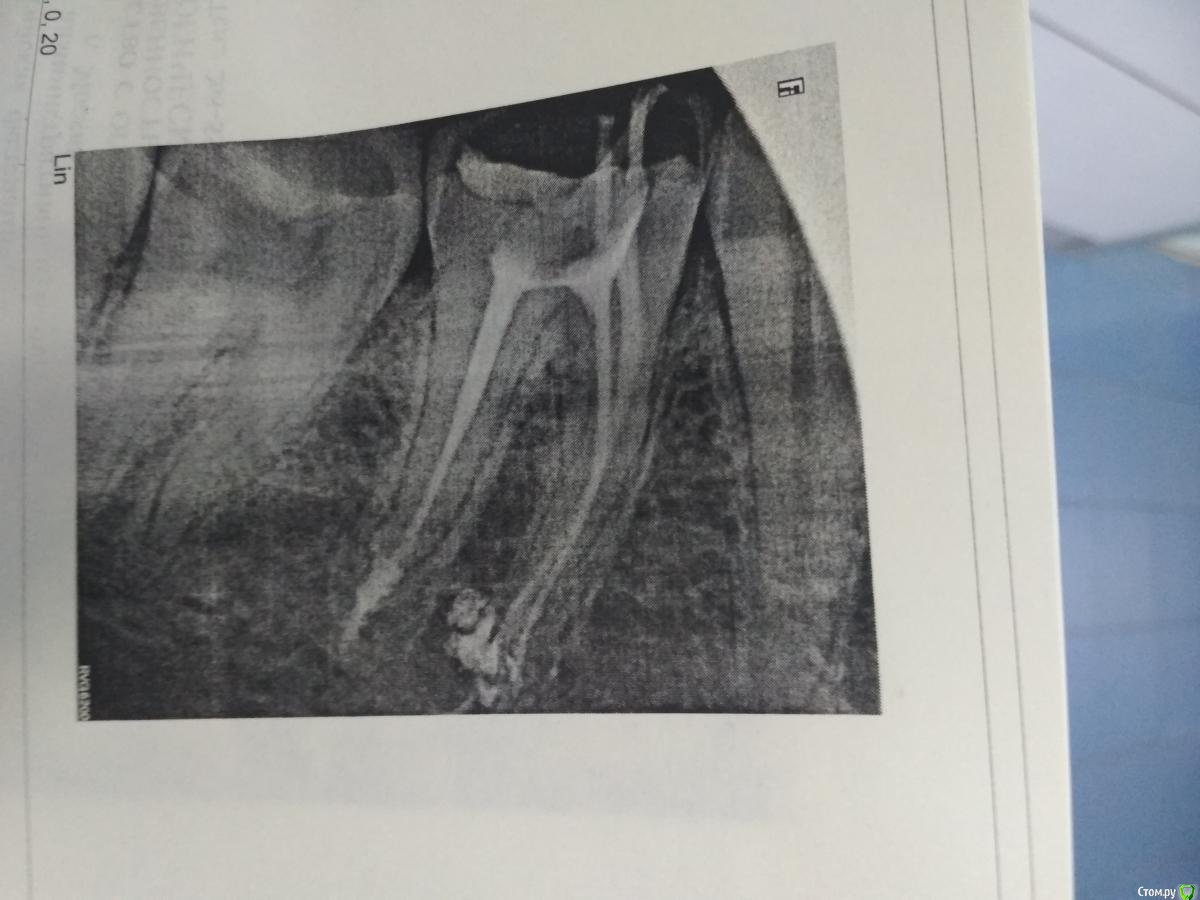

Павел777 Опубликовано 31 января, 2018 Поделиться Опубликовано 31 января, 2018 Здравствуйте!Пошел в клинику менять пломбу, врач удалил нервы, стал чистить каналы. Первый снимок был обычным, а второй вот такой. Смущает что-то непонятное в районе дна каналов. Это нормально или что-то пошло не так?Если не так, то что это такое и что теперь делать? Заранее спасибо за ответы! Ссылка на комментарий

red_butler Опубликовано 31 января, 2018 Поделиться Опубликовано 31 января, 2018 Это силер (пломбировочный материал), если жалоб нет, то не страшно Ссылка на комментарий

red_butler Опубликовано 31 января, 2018 Поделиться Опубликовано 31 января, 2018 Большое спасибо! Вы меня успокоили не за что, протезируйте зуб и диспансерно наблюдайте, через пол года сделайте снимок. Ссылка на комментарий